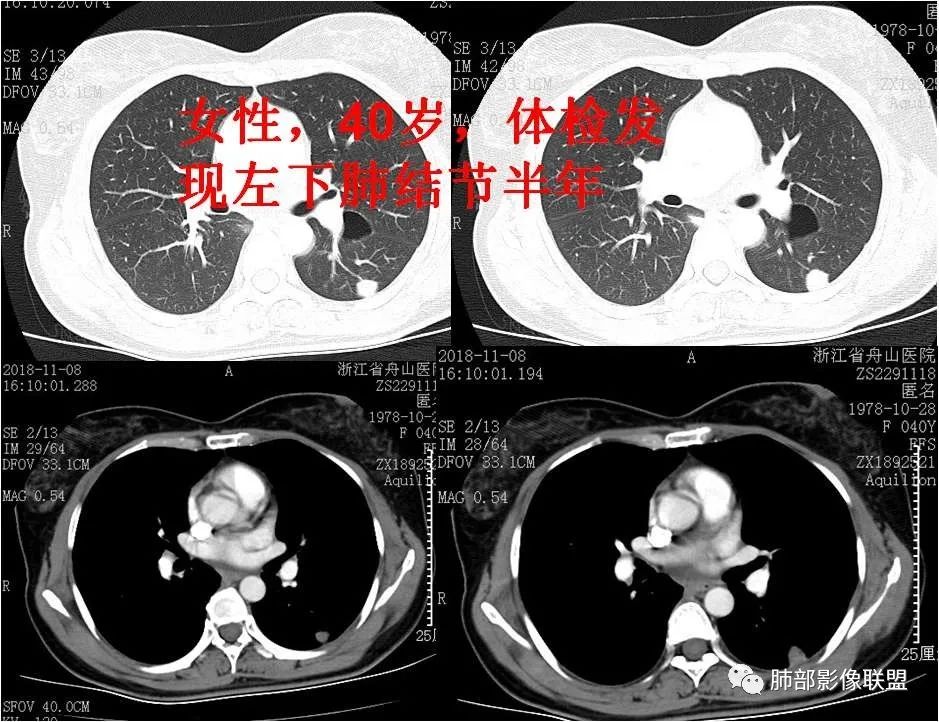

例一.女性,四十岁,体检发现肺结节半年。 医学百科网 | YxBaike.Com

半年前的CT,病灶有轻度增大。

病例一,病灶呈实性结节,表面光滑,无分叶及毛刺,密度均匀,与胸膜关系较密切,胸膜表面重建显示“空洞”,无“星芒样”改变。良性结节?肿瘤? 医学百科网 | YxBaike.Com